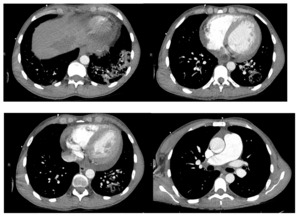

The patient is a 32-year-old male with a history of end-stage renal disease on hemodialysis secondary to a distant history of poststreptococcal glomerulonephritis who presented to the emergency department due to hemoptysis. He reported that two weeks prior he had a similar episode but it self-resolved. He had no fevers or sick contacts. Family history revealed that he had a sibling who recently expired from pulmonary complications of dermatomyositis. The patient was in clear distress from persistent hemoptysis with evidence for upper airway edema including stridor and hoarseness. He experienced brief syncope twice. Due to his presentation and concerns of instability we discussed intubation with our patient and he expressed hesitancy and became emotional due to his sibling’s recent passing following intubation. Alternative measures for stabilization were considered and nebulized tranexamic acid was administered. This resulted in swift improvement of coughing episodes and resolution of hemoptysis. The intensive care unit was consulted, and the patient was admitted in stable condition. There was no relapse of hemoptysis during his hospital course. During admission, the patient was electively intubated for bronchoscopy with cryotherapy for clot removal from the upper and lower airways. Chest radiography demonstrated interstitial opacities of the lung bases bilaterally (Figure 1). Chest computed tomography angiography confirmed left lower lobe pneumonia with cavitating pulmonary nodules, without evidence of pulmonary embolism (Figure 2). Autoimmune workup was significant only for myeloperoxidase antibodies. Respiratory culture was positive for P. aeruginosa and Methicillin-sensitive S. aureus. The patient was diagnosed with hemorrhagic pneumonia, treated with broad spectrum antibiotics, and discharged with follow-up for further outpatient workup.

Left lower lobe pneumonia.

Cavitating pulmonary nodules measuring up to 15 mm in mean diameter, suspicious for septic emboli or cavitary pneumonia. Cavitating metastases are also in the differential diagnosis. Additional non-cavitating pulmonary nodules measuring up to7 mm.

Cardiomegaly and small to moderate-sized pericardial effusion.

Enlargement of the main pulmonary artery is suggestive of pulmonary hypertension.

No evidence for pulmonary embolism